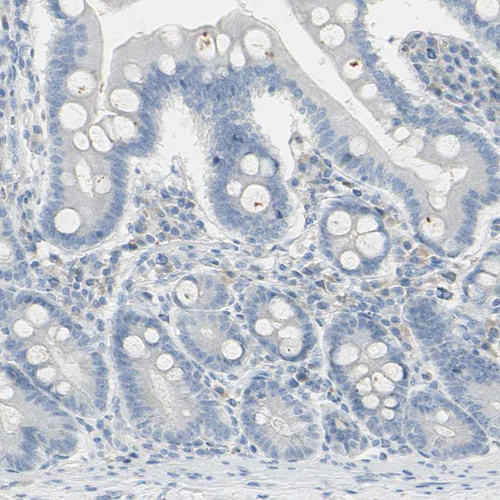

Immunohistochemical staining of human duodenum shows no positivity in glandular cells as expected.